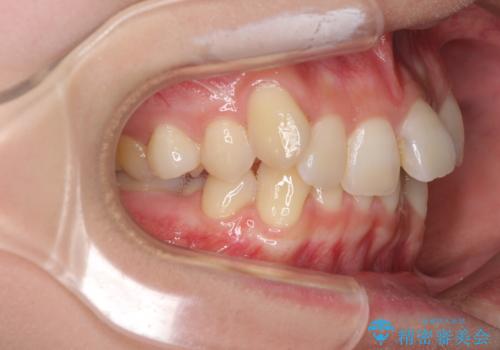

- 前歯の叢生と八重歯を気にして来院された患者様です。

叢生が強く、奥歯の咬合も左右差が大きかったため、上下左右4本を抜歯して、ワイヤー矯正を行うこととしました。

20歳前後と年齢が若かったため、非常にスムーズに歯列が整い、1年半をかけずに治療を終えることができました。